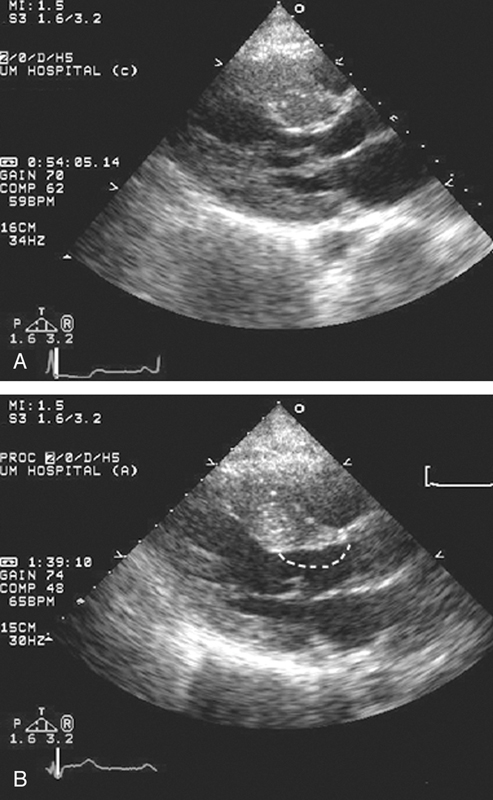

فحوصات تشخيصية لبعض امراض القلب والشرايين التاجية